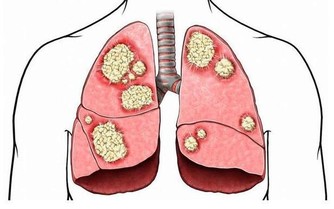

過敏表現常在接觸過敏原半小時至數小時後出現。一般表現如下:煩躁、心慌、胸悶、咽部不適、視物模糊、疲勞、易激惹、緊張、自控力下降、忍耐力下降、情緒失控、皮膚潮紅、紫癜、皮疹、耳道濕潤、鼻塞、鼻涕、鼻塞、噴嚏、眼瞼浮腫、腹痛、腹瀉、多汗、咳嗽,哮喘,呼吸淺快、血壓降低、關節冷痛等等。可見於多種過敏性疾病(如過敏性哮喘、咳嗽、紫癜、皮炎、鼻炎)、一些易激綜合徵(比如腸易激,還有情緒易激等等)、濕疹、痛經、咽炎等等。

過敏體質的本質都是陽虛的,甚或有陽虛肝鬱。這一類人都是敏感體質,包括對自身及外界物質、環境、狀況、境遇都不能很好的適應,從而出現癢、痛、瘡等等表現。我們不能不想到一句經典的詞語“諸痛癢瘡,皆屬於心”。其一般表現如下:怕冷、怕熱、手足發涼、自汗、煩躁、心慌、胸悶、咽部不適、視物模糊、入睡困難或嗜睡、易疲勞、易激惹、緊張、驚悸、自控力下降、忍耐力下降、情緒失控、失眠、多夢、皮膚潮紅、皮疹、耳道濕潤、鼻塞、鼻涕、鼻塞、噴嚏、眼瞼浮腫、腹痛、腹瀉、腹脹、納差、脅痛、易感、咳嗽、咳吐涎沫、哮喘、小便頻多、舌淡體大或有齒痕、脈象沉細或結代等。